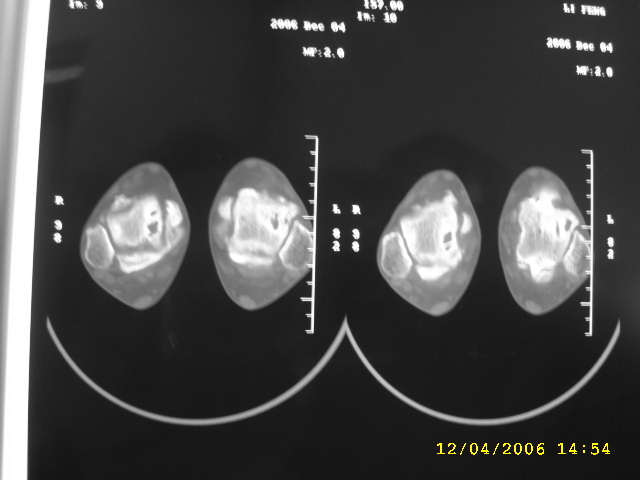

男,44,双踝关节肿胀,疼痛,活动受限2月余。无外伤史。

双侧距骨及胫骨都有骨质破坏,还很对称,最好追问一下病史,看这人有没有痛风。

双侧距骨可见多发囊变区,边缘硬化内可见更高密度影,考虑1双侧踝关节结核2退行性骨关节病

双侧距骨关节面下可见多发囊变区,边缘硬化内可见更高密度影。考虑:双踝剥脱性骨软骨炎。

双侧距骨及胫骨都有骨质破坏,边缘硬化内可见更高密度影,双侧对称性发病,踝关节及跟距关节内低密度影(气体影?),双侧对称发病基本可以排除关节结核及化脓性关节炎,痛风性关节炎以第1跖趾关节为典型发病部位,临床症状间歇性发作,受累关节非对称性肿胀与本例不符,首先考虑退行性骨关节病,请结合抗\"o\"及类风湿因子检查排除风湿性关节炎。

踝关节及跟距关节内气体影为真空现象。

跟进!关节间隙明显变窄,诸相对骨性关节面增生、硬化,内见多发囊变,考虑增生性骨关节病!

双侧距骨及胫骨近关节面都有骨质破坏,边缘硬化,唇样变,内可见囊状低密度影,双侧对称性发病,首先考虑退行性骨关节病。